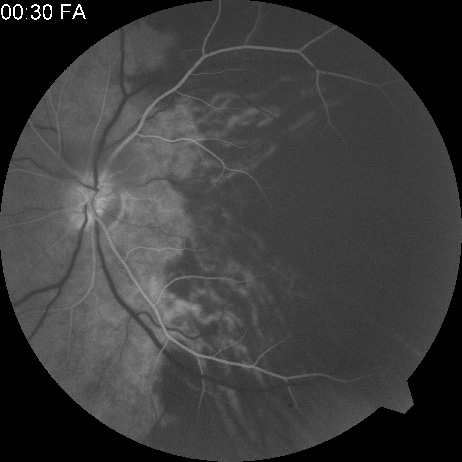

The clinical picture is typically striking. Patients present with a sudden painless loss of vision. The appearance of a cherry-red spot in the fundus is characteristic (Fig. 1).2 The cherry-red spot appears because soon after obstruction of the blood flow to the inner retina, the normally transparent retina becomes opaque and blocks the brownish-red color from the underlying choroid, which is still supplied by blood. Because the retina overlying the foveola is relatively thin, however, the normal color of the choroid is still visible in this area.3,4 Although characteristic, the cherry-red spot is not pathognomonic for central retina artery obstruction.5 Sometimes the characteristic cherry-red spot does not develop; there may be only a slight accentuation of the brownish-red color in the foveola.4 It is not known how long it takes this cherry-red spot to appear, but in a primate model, it has appeared as early as 30 minutes after obstruction.6 An afferent pupil defect is usually present.2

Fig. 1. A: Acute central retinal artery obstruction with a cherry-red spot. B and C: Intravenous fluorescein angiography. There is a delay of dye appearance in the central retinal artery, and when it does appear, it does not fill the arteries completely. D: Ocular coherence tomography (OCT) at the time of occlusion showing the increase in retinal thickness and reflectivity of the inner layers of the retina. E: Seven months later there is significant optic atrophy(G), and the OCT (F) shown now has marked thinning of the retina.

Intravenous fluorescein angiography is useful in showing the details of the abnormal circulation of a central retinal artery obstruction (Fig. 1). The principal abnormality is the delay in the appearance of the dye in the central retinal artery and its branches.2 Rather than the central retinal artery and its branches filling rapidly, considerable time may elapse before the entire arterial system is filled.15 The filling of the retinal arteries is often abnormal, with the fluorescein partially filling an artery (a dye front) or hugging the vessel wall, as in normal venous filling.15

Segmentation of the blood column is often well defined on fluorescein angiography.15 Venous filling is usually slowed and occasionally the dye does not progress beyond laminar flow during the study.14 In approximately 10% of eyes that have central retinal artery obstruction, there are abnormal choroidal filling defects, reflecting posterior circulation obstruction. These defects can occur even in patients who appear to have a typical central retinal artery obstruction.14 Leakage of dye from the vessel walls is not normally seen except at the site where an embolus lodges within a retinal artery.16 With time, the flow within the artery and its branches is reestablished and the appearance of the intravenous fluorescein angiogram may return to normal.

Optic coherence tomography (OCT) of an acute central retinal artery occlusion shows a slight increase in the thickening of the retina and reflectivity of the inner layers of the retina that correspond to the opacity seen clinically (Fig. 1).409 With time, the disc becomes atrophic and the retina thinner.